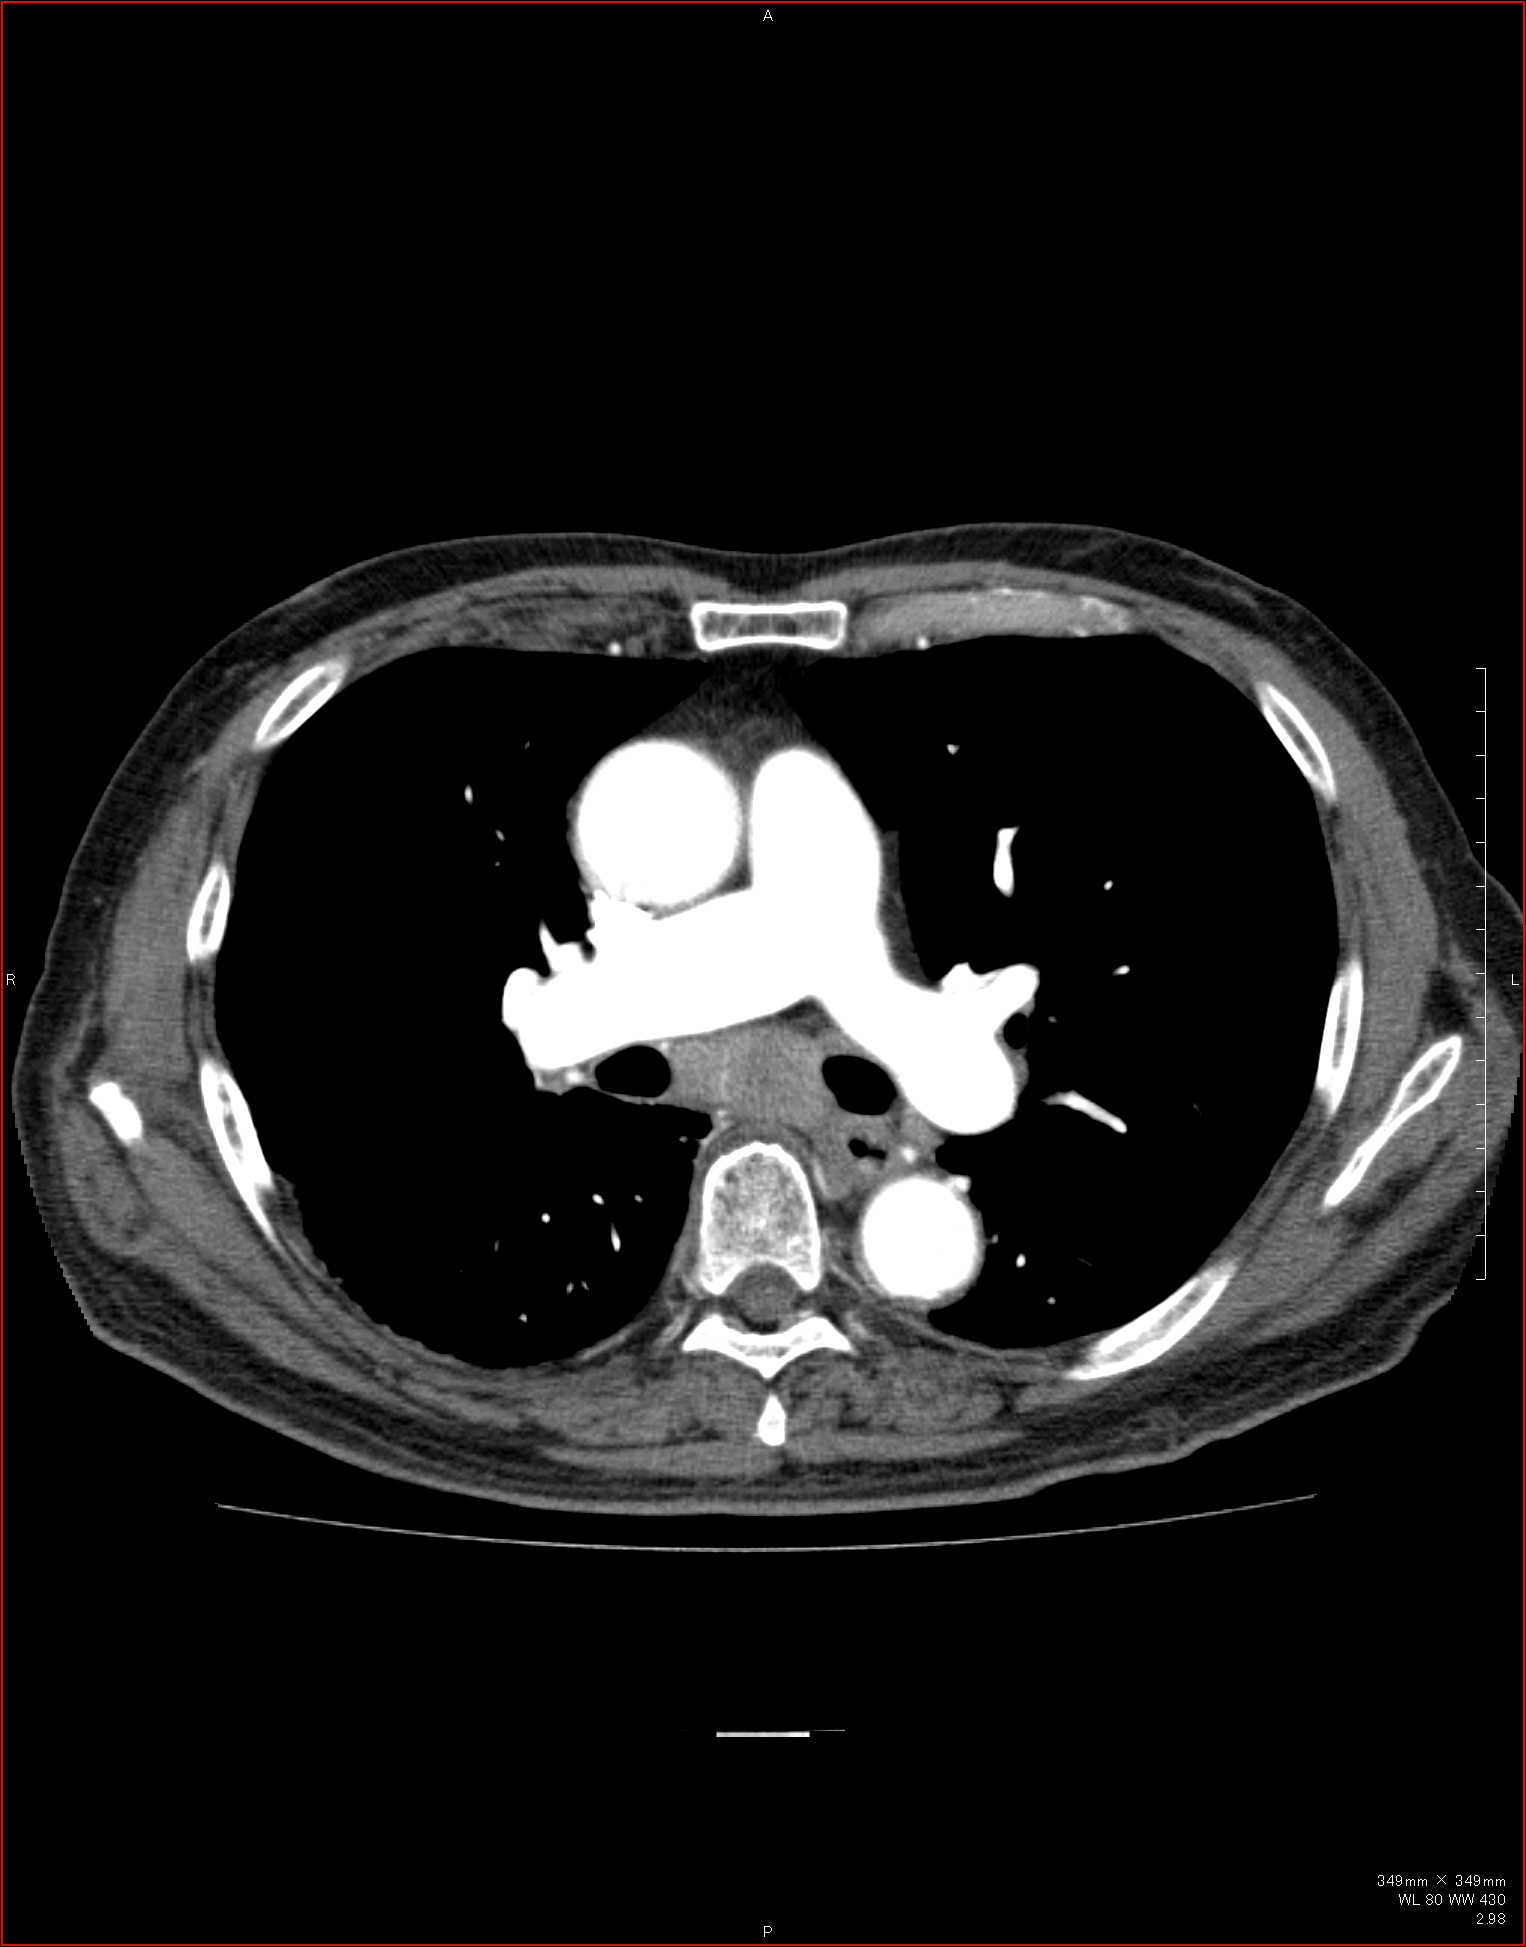

CTで見ると…

3Dだと、こうなります。

気管狭窄ですね。こういう所見もレントゲンで捉えることができるのです。